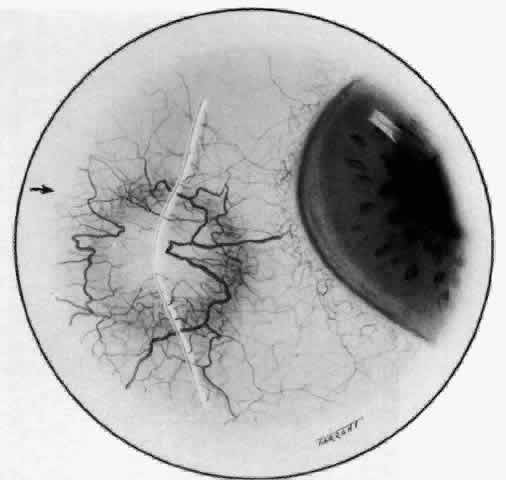

The characteristic features of necrotizing scleritis on fluorescein angiography

are hypoperfusion and, eventually, nonperfusion of the vascular

networks (Figs. 40 through 43).26 The initial changes are on the venous side of the capillary network; the

transit time of the dye increases even if the eye is red and congested. If

the disease process persists or has been present for a long time, thrombosis

and permanent vaso-occlusive changes occur. These vessels (or

the occluded capillary network) are bypassed by the opening of

anastomotic channels. New vessels in a granuloma give rise to deep intrascleral

leakage of dye (see Fig. 43). Conjunctival and episcleral involvement by the destructive change is

Fig. 41. Late stage of fluorescein angiogram adjacent to the site of necrosis in

the same patient as in Figure 40. Although the eye is uniformly congested, the area near the necrosis shows

vascular shutdown, whereas the rest of the conjunctiva and episclera

is normally perfused. Fig. 41. Late stage of fluorescein angiogram adjacent to the site of necrosis in

the same patient as in Figure 40. Although the eye is uniformly congested, the area near the necrosis shows

vascular shutdown, whereas the rest of the conjunctiva and episclera

is normally perfused.

Fig. 42. Late arterial phase of fluorescein angiogram in a patient with necrotizing

scleritis. All the vessels except the main trunk and the vessels around

the limbal perforating vessels are occluded and remain unperfused

throughout the angiogram. Fig. 42. Late arterial phase of fluorescein angiogram in a patient with necrotizing

scleritis. All the vessels except the main trunk and the vessels around

the limbal perforating vessels are occluded and remain unperfused

throughout the angiogram.

Fig. 43. Late venous phase of angiogram of a patient with necrotizing scleritis

showing late deep leakage from vessels on the surface of the sclera and

leakage of the capillary network at the limbus and the vessels draining

it, together with poor or absent perfusion of the remaining vessels. Fig. 43. Late venous phase of angiogram of a patient with necrotizing scleritis

showing late deep leakage from vessels on the surface of the sclera and

leakage of the capillary network at the limbus and the vessels draining

it, together with poor or absent perfusion of the remaining vessels.